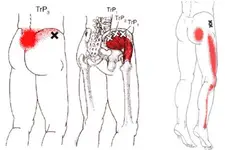

Bel Fıtığı ve Platin Takılması: Genel BilgilerBel fıtığı, omurganın aşağı kısmında yer alan disklerin (intervertebral disklerin) yıpranması sonucunda oluşan bir rahatsızlıktır. Bu durum, diskin içindeki jel benzeri maddelerin dışarı çıkması ve sinirlere baskı yapmasıyla karakterizedir. Bel fıtığı, sırt ağrısı, bacaklarda uyuşma, güçsüzlük ve hareket kısıtlılığı gibi belirtilerle kendini gösterir. Platin Takılması: Neden ve Nasıl Uygulanır? Bel fıtığı tedavisinde, cerrahi müdahaleler gerekebilir. Bu tür durumlarda, omurga stabilitesini sağlamak amacıyla platin (metal veya biyomateryal) takılması tercih edilebilir. Platin, omurga yapılarını bir arada tutarak iyileşme sürecine destek olur. Platin Takılmasının Zararları Platin takılmasının bazı potansiyel zararları ve komplikasyonları şunlardır:

Alternatif Tedavi Yöntemleri Bel fıtığı için platin takılması dışında birçok alternatif tedavi yöntemi bulunmaktadır: